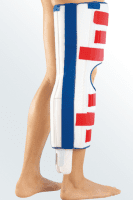

Medi Knieruhigstellungsschiene PTS weiß-blau-rot

Artikelnummer:

501496

Hersteller:

medi GmbH & Co. KG